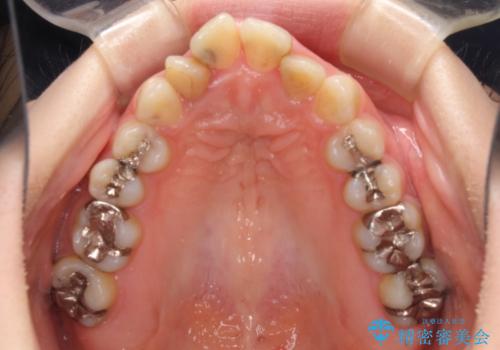

全体的にむし歯や欠損が多く、矯正治療とは別に処置が多く必要な口腔内でした。

口元の突出感を改善するために小臼歯4本を抜歯することとしましたが、左下は大臼歯が欠損していたため、そのスペースを活用し、小臼歯を3本抜歯して治療を行うこととしました。

目立たないハーフリンガル矯正を希望され、裏側装置はどうしても清掃性が低下し、むし歯発生のリスクが高まるため、矯正治療前にしっかりとむし歯治療を行い、矯正治療後にセラミックによる補綴治療を行うこととしました。

抜歯したスペースがなかなか閉じず、治療に時間はかかりましたが、術前術後のむし歯治療と合わせて3年10ヶ月で治療を終えることができました。

途中結婚により遠方に引っ越しをされたため、むし歯治療は取り急ぎ目立つところをセラミッククラウンとしましたが、今後落ち着いてきたら他の部分も行っていく予定です。